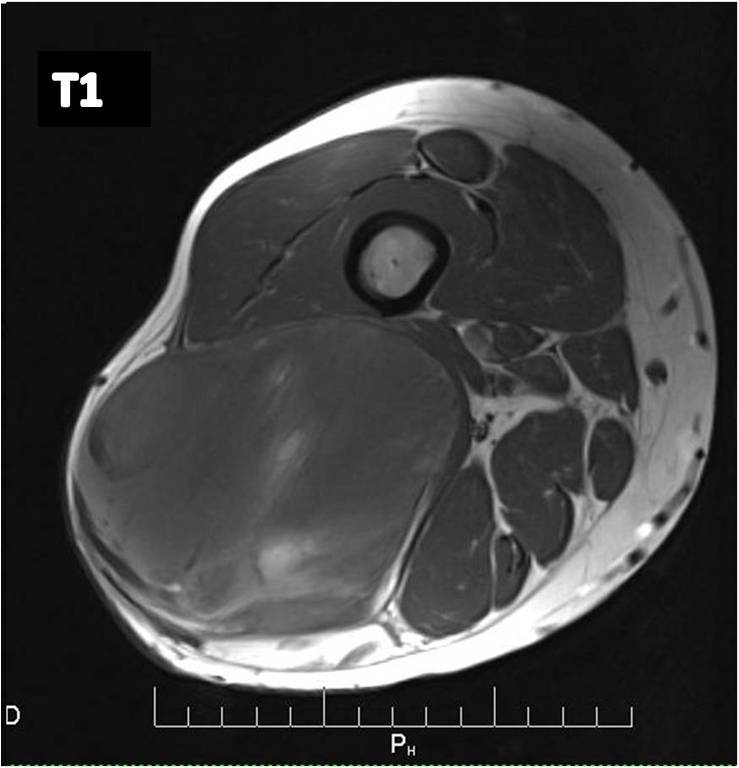

MRI (Fig. 2 and 3)

• Large well defined multilobulated mass.

• Low signal on T1 weighted images. Usually adipose tissue composes less than 10 percent of the tumor and is difficult to detect on an MRI as high signal on T1W images. (Fig. 2A)

• Marked high signal on T2 weighted sequence. (may mimic a synovial cyst) (Fig. 2B) The myxoid/mucinous tissue consists of mucopolysaccharides that holds onto water and shows up high signal on T2W images.

• Identification of the subtle fat requires comparison of T1W and T2W images in the same plane but is usually very difficult to discern. (Fig. 2)

Fig 2. T1-weighted MR image (A) of a myxoid liposarcoma demonstrates well-defined mass of intermediate signal intensity with central areas of high intensity. T2 –weighted fat-suppressed image (B) heterogeneously mostly high signal intensity within the lesion.